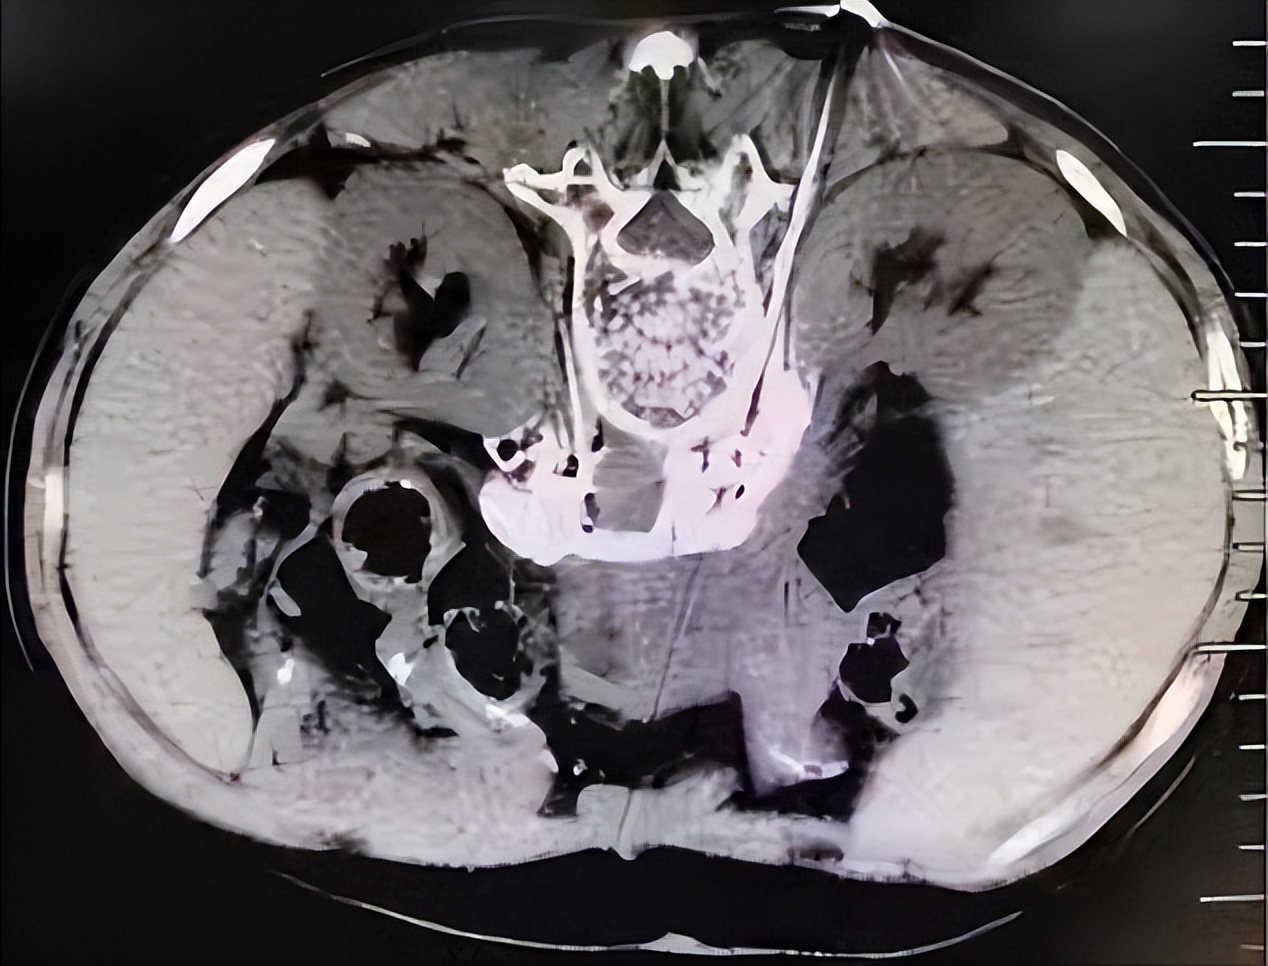

经穿刺针注射无水乙醇以毁损神经

CT引导下注入无水乙醇